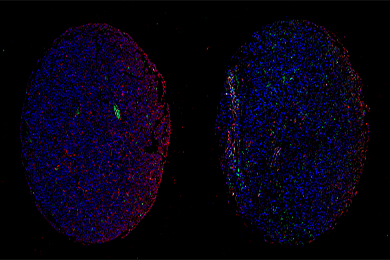

陕西依科生物技术服务有限公司病理吉林图片分析是病理技术服务中不可缺少的一部分,病理图文分析系统的推出有效地减轻了操作人员的劳动量。高分辨率显示器下观察模式几乎完全代替了头晕目眩的镜下观察模式。工作人员的颈椎、眼睛不易疲劳。同时大幅度提高工作效率,提升整体水平。病理图像分析系统又称:显微医学影像工作站;显微影像软件;病理图文分析系统;病理图文报告系统;病理医学影像工作站;病理图文工作站;病理工作站;病理影像工作站;病理图文工作站软件等。它采用先进的图像处理技术与高精度硬件配置,从系统信号的获取、测量、处理到打印输出全部实现彩色化、自动化、智能化,具有操作简便、图像处理功能强、图像分析智能化、图像清晰度高、图文报告打印快捷、数据库管理功能强大等优点。为临床病理、药理病理及所有运用显微镜的科技工作者提供了具有划时代意义的先进工具。